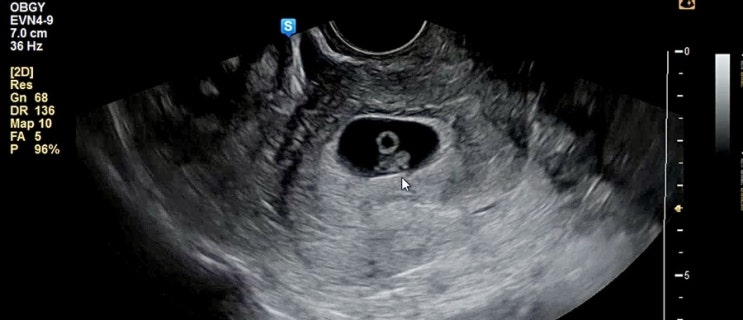

7주1일 심장소리, 아기 크기

지난 주 6주 1일 때 처음 심장소리를 들었다. 아마 103bpm이었는데 일주일 후인 오늘 가보니 심장박동수가 ...